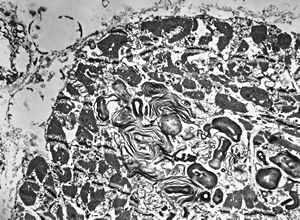

M,45y. | Fabry disease - myocardium

F, 62y. | myxoma atrii